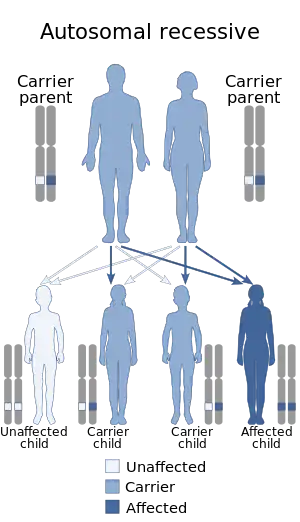

| Joubert syndrome is inherited via an autosomal recessive manner | |

Joubert syndrome is a rare autosomal recessive genetic disorder that affects the cerebellum, an area of the brain that controls balance and coordination.

Joubert Syndrome is known to affect 1 in 80,000-100,000 newborns. Due to the variety of genes this disorder involves, it is likely to be under-diagnosed. It is commonly found in Ashkenazi Jewish, French-Canadians, and Hutterite ethnic populations. Most cases of Joubert syndrome are autosomal recessive; in these cases, both parents are either carriers or affected. Rarely, Joubert syndrome is inherited in an X-linked recessive pattern. In these cases, males are more commonly affected because they must have one X chromosome mutated, while affected females must have mutated genes on both X chromosomes.[12]